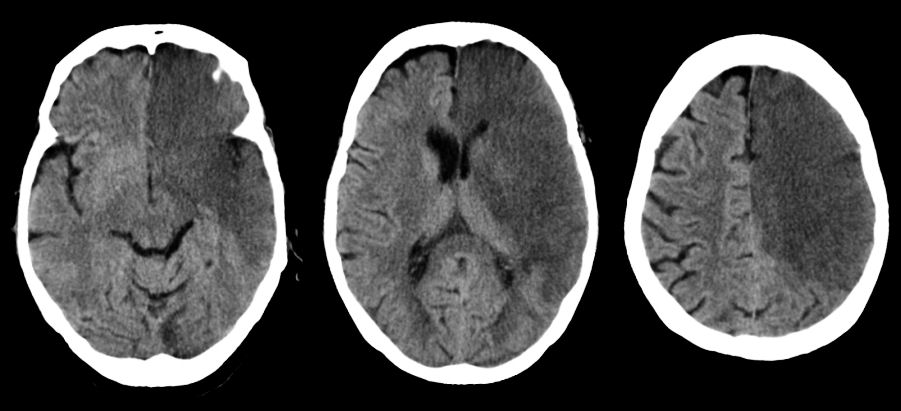

Иллюстрации и пояснения: гиподенсивный очаг на КТ головного мозга